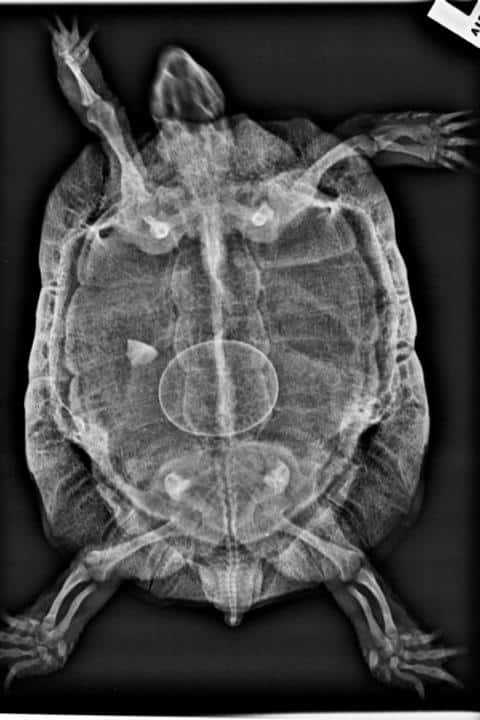

Das Röntgenbild zeigte 6 Eier, wovon 1 Ei im Becken steckte. Es bestand akute Lebensgefahr. Nur durch einen stationären Aufenthalt mit fachgerechter Behandlung hatte mein Weibchen eine Chance, dies zu überleben. Nach einem ausführlichen Aufklärungsgespräch übergab ich meine Schildkröte Herrn Friz, mit vollem Vertrauen, er würde alles tun, um ihr Leben zu retten.

Somit wird sehr häufig auf das Wehen auslösende Hormon Oxytocin zurückgegriffen. Und in vielen Fällen sorgt dies dafür, dass die Eier zeitnah bis unmittelbar nach der „Wehenspritze“ gelegt werden. Doch nicht selten kommt es hierbei zu Komplikationen, die in vielen Fällen gar nicht erkannt werden: übertragene Eier bleiben im Becken stecken, Eier werden aufeinander geschoben, so dass es zum Schalenriss, manchmal auch dem Riss des Legedarmes kommt. Ist das Becken nicht auf die Eiablage vorbereitet und somit zu eng, können Eier in die Harnblase, in den Enddarm, bei Wasserschildkröten auch in die beiden als Wassertanks dienenden Analblasen rutschen. Dass es hierzu gekommen ist, wird dann nur bei weiteren Röntgenaufnahmen entdeckt.